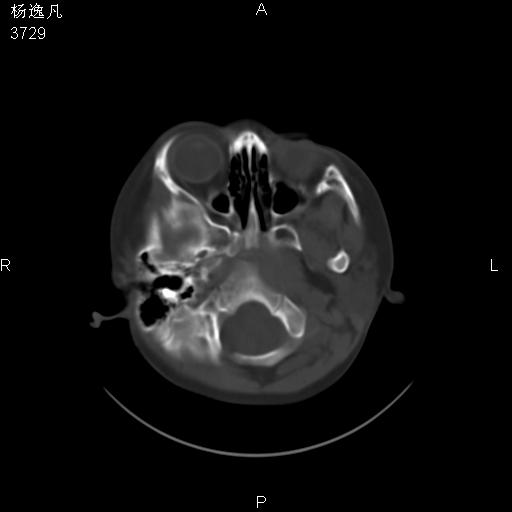

男性,5岁,面部受外伤,余无特殊

骨窗

1、右面部及颞部软组织肿胀。

2、腺样体肥大。

头颅ct平扫未见明确外伤性征象,右侧面部及颞部软组织肿胀,后鼻腔软组织影增大,增厚,鼻咽顶部变窄,考虑鼻咽腺样体增值肥厚。

双侧位置太不对称,未见明显骨折征象。